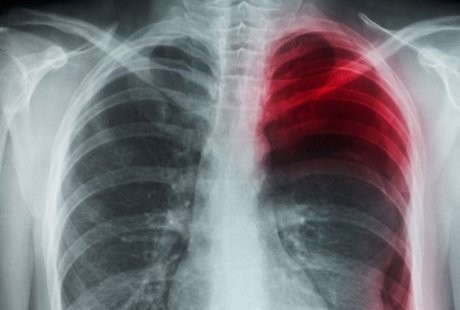

Ia langsung pergi ke Central Hospital of Wuhan dan dokter mendiagnosanya mengalami pneumotoraks spontan atau kolaps paru-paru, yang terjadi ketika udara menjadi terperangkap di samping paru-paru.

Sebagian besar kasus pneumotoraks terjadi secara spontan dan pada pria muda. Beberapa kasus berkembang karena cedera dada atau penyakit paru-paru, kadang juga karena adanya luka kecil di paru-paru.

Gejala pneumotoraks yang paling umum adalah rasa nyeri secara tiba-tiba, nyeri dada yang tajam, diikuti dengan nyeri selama inhalasi (menarik napas).

Dalam kebanyakan kasus, kolaps paru-paru bisa sembuh tanpa perlu pengobatan, tetapi kebutuhan udara yang terjebak perlu dibersihkan jika menyebabkan masalah dengan pernapasan. Kondisi tersebut terjadi pada sekitar 2 dari setiap 10.000 orang dewasa muda, tetapi pria empat kali lebih mungkin mengalaminya dibandingkan wanita.